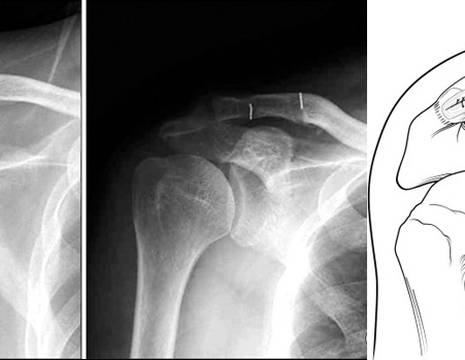

​Dopo un trauma a livello della spalla si può avere una lussazione dell'articolazione acromion-claveare, con i legamenti coraco-claveari e acromion-claveari rotti e il deltoide disinserito

Trauma spalla con lussazione acromion claveare

Trauma alla spalla con lussazione acromion claveare

Una radiografia della spalla (a volte effettuata in comparativa con la spalla contro laterale) è nella maggior parte dei casi sufficiente per diagnosticare una lussazione acromion claveare. La radiografia mostra l’incongruenza tra la clavicola, che non è più trattenuta dai legamenti coracoclavicolari e l'acromion, oltre che un aumento della distanza coracoclavicolare.